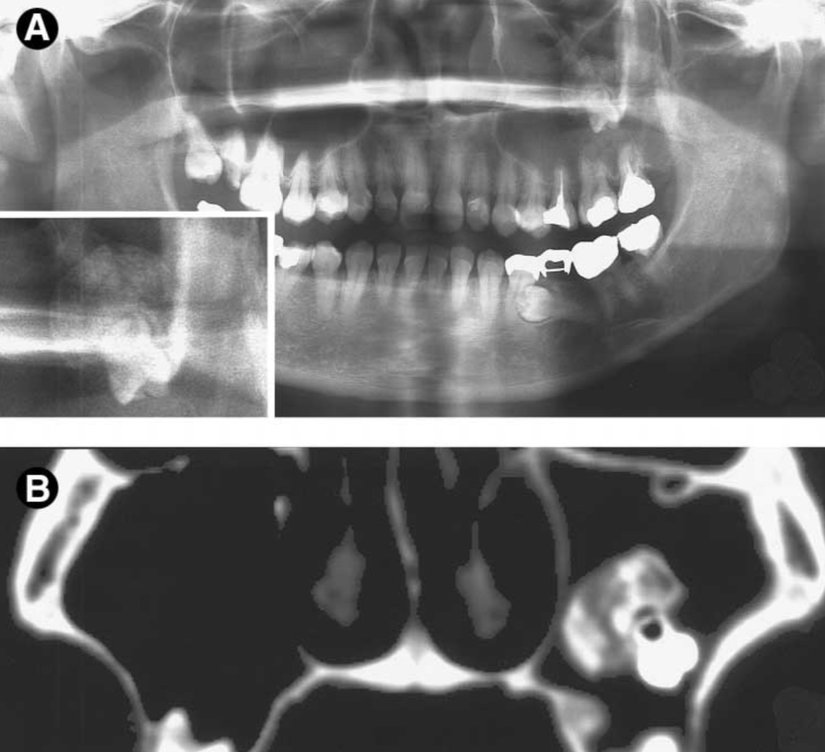

Yukarıdaki vakada fazla uzaklaşmamış bir 20 yaş dişi, hastada herhangi bir şikayete neden olmadığından bulunduğu yerde öylece bırakılmasına karar verilmiş.

Dışarıdan bakıldığında diş gözükmese bile radyografik ve histopatolojik incelemelerde dişe rastlanılan bir vaka. “Teratom”un nadir bir çeşidini gördüğümüz bu vakada, totipotent hücrelerin diş benzeri hücrelere farklılaşmış olduğunu anlıyoruz.